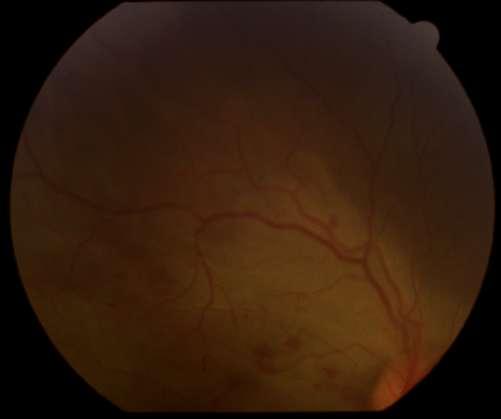

ü OD: Lesión blanquecina a temporal de la mácula, vecina a fóvea (Imagen A)

ü OI: Lesiones blanquecinas granulares y hemorrágicas en arcada temporal superior (Imagen B)

Torres JP, López JP. Necrosis retinal aguda: una entiedad de adultos en pediatría. Rev Chil Infect 2007; 24(4) 327-330

A B

1.F. NECROSIS RETINAL AGUDA BILATERAL (NRA) POR CITOMEGALOVIRUS (CMV)

Caso aportado por Tomás González

NECROSIS RETINAL AGUDA POR CMV

ü La necrosis retinal aguda es una panuveítis, que en el caso descrito a continuación se dio en un pacientede 4 años inmunosuprimido

ü CMV es una causa inhabitual de NRA

ü Puede ser unilateral o bilateral asincrónica Clínica

ü Áreas de necrosis retinales focales, bien delimitadas en la periferia, más allá de la arcada vascular temporal

ü Rápida progresión de la necrosis, circunferencial, cuando no se instaura tratamiento antiviral

ü Evidencia de vasculopatía oclusiva con compromiso arteriolar

ü Reacción inflamatoria vítrea y de la cámara anterior.

ü Otras características menos frecuentes incluyen la neuropatía óptica y escleritis.

Caso clínico

ü Niño de 4 años, con antecedentes de púrpura trombocitopénica amegacariocítica, recibe transplante de progenitores hematopoyéticos. Sin embargo, paciente evoluciona con infección sistémica por CMV por lo que se decide iniciar tratamiento con Foscartet EV (actualemente está en su 7º día de tratamiento).

ü Por lo anterior se solicita evaluación por oftalmología para descartar compromiso ocular.

Examen Físico

AV: no coopera

PIO no registrado

Fondo de ojos: